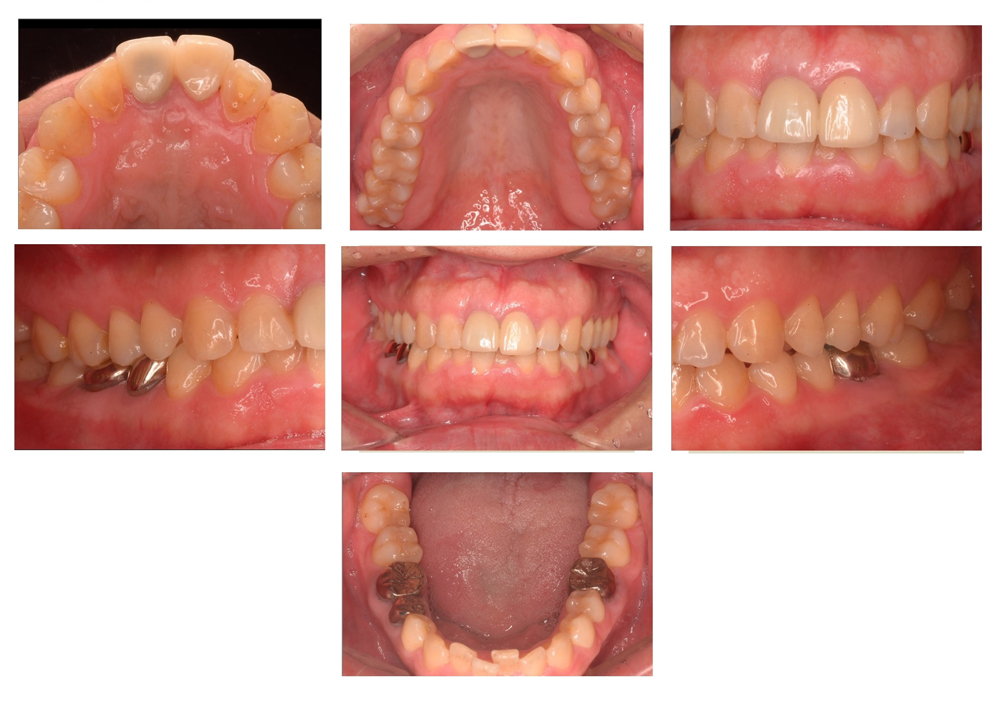

④重度の歯周病で多数の抜歯に至ったケース

【60歳 男性】

重度の歯周病のため多数の歯が抜歯となりました。

入れ歯は入れたくないという患者の要望にお応えすべく、残った歯に対する歯周病治療

+ 左右の上顎臼歯部に対する増骨手術 +

インプラント治療を実施しました。

治療の結果、入れ歯の装着は免れましたが、このような複雑なケースでは歯とインプラントの維持のために定期的なメンテナンスを行うことがより一層重要となります。

このケースでは、歯科治療終了後に内科的疾患のため唾液の分泌量が減少したことにより、むし歯が発生しやすい状況となり、改めてメンテナンスの重要性が痛感されました。